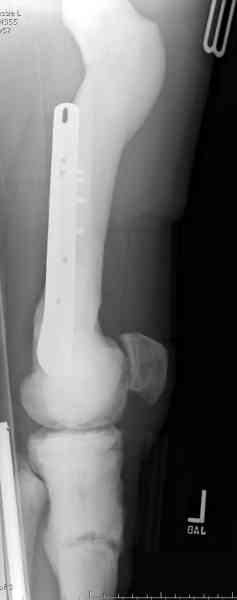

Конечно, было бы идеальным применение интрамедуллярного остеосинтеза, но учитывая прежний собственный опыт (лечил перелом бедра) и

публикации, предупреждающие о трудностях при обработке кости (иногда из-за неподготовленности инструментария результатом была неадекватная фиксация перелома, или перенос операции из-за фактора усталости оперирующего персонала), решили применить пластину (и в этом же случае был выбран Synthes plate, так что представитель за два дня

зароботал... на десерт тоже).

Заказаны были дополнительные различные дрели, и на следующий день, усиленной бригадой, больного прооперировали, потратив на каждое отверстие около 25-35 минут, хотя сверлили с охлаждением по нарастающей по диаметру сверл и с их заменой каждые 2 мм сверления.

Теперь стоит задача со сращением перелома, из-за отсутствия литературных данных по применению костных стимуляторов при остеопетрозе, и не зная как поведет в этой среде Grafton, все таки надеюсь, что даст толчок к стимуляцию, решил применить пастообразную деминерализованную костную матрицу, расположив спереди между отломками.